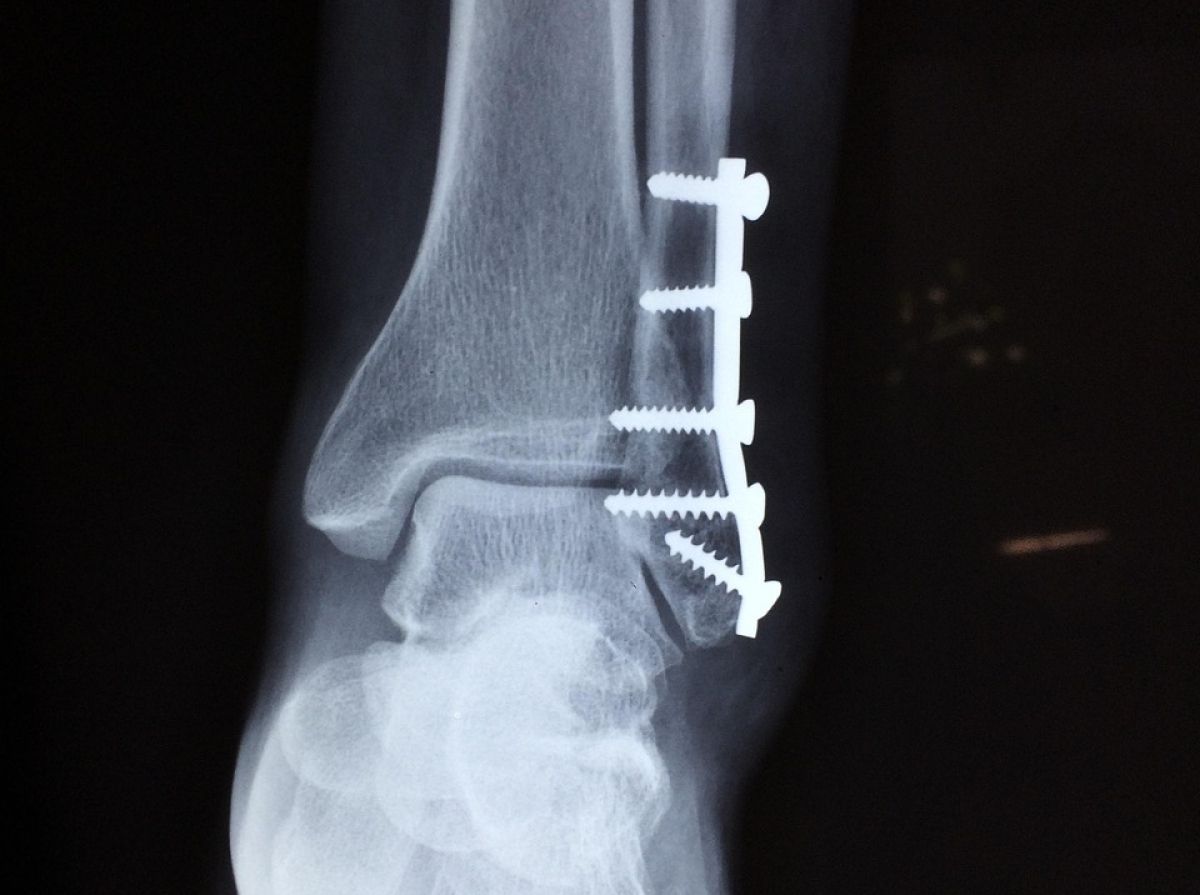

Pri zahtevnejših poškodbah, zlasti če gre za več delov zloma ali poškodbe mehkih tkiv, je potrebna odprta repozicija. V tem primeru kirurg med operacijo kost neposredno naravna in jo stabilizira z vijaki, ploščicami ali palicami. Takšna stabilizacija omogoča natančno poravnavo in hitrejše okrevanje.

Vijaki se uporabljajo za stabilno pritrditev kostnih odlomkov in ohranjanje pravilnega položaja med celjenjem.